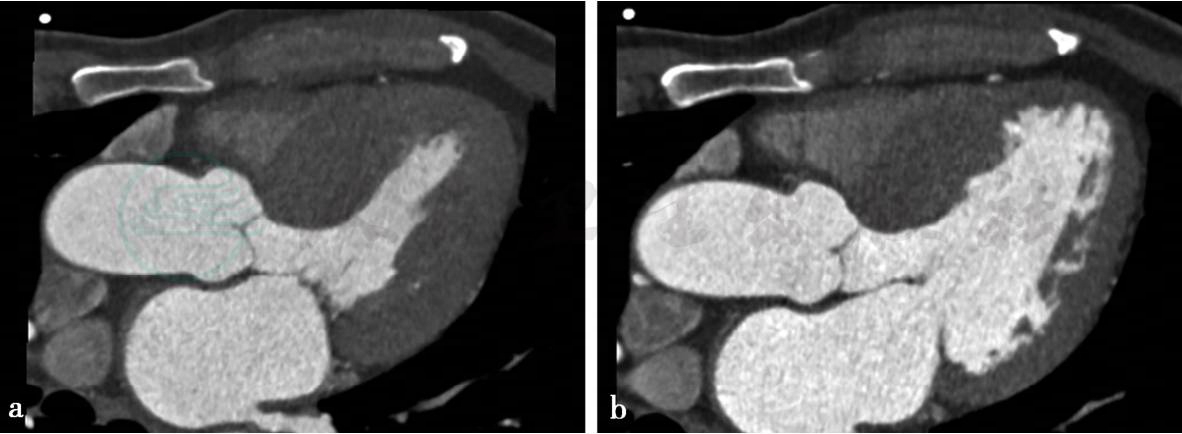

病例3:心脏CTA扫描四腔位收缩期与舒张期。

图1 图1a,左心室于收缩期显示心肌壁明显增厚,室间隔厚约4cm,以室间隔尤重。图1b,左心室于舒张期显示心肌壁增厚,室间隔厚约2.4cm,左心室舒张功能减弱